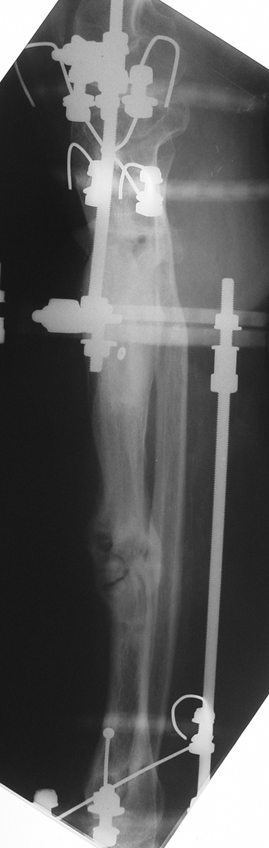

Vaka 2